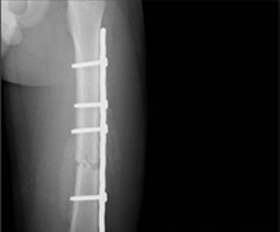

- 경골 간부 골절 > 금속판 : 12~18개월 / 골수정 : 18~24개월

- 금속판

- 골수정